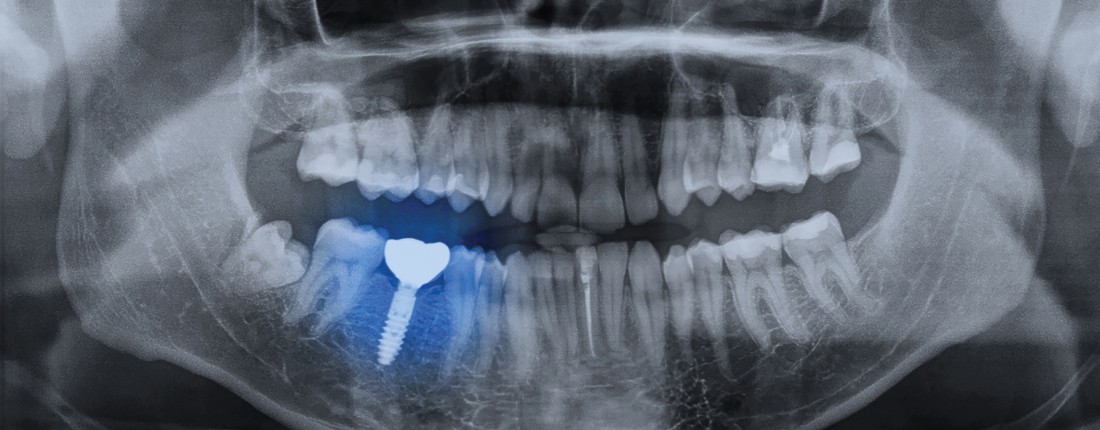

All-on-4 implants are made of metal—usually titanium—and are surgically screwed in on top of four posts on the jawbone. These posts are anchors for attaching your replacement teeth, so you no longer have to worry about removing the implant at night or having difficulty speaking or chewing. Enjoy complete support, confidence, and convenience with all-on-4 dental implants from Southfield Family Dental.

As the name suggests, all-on-4 implants only use four implants to replace the teeth on an upper arch, whereas traditional implants utilize anywhere from five to eight. Additionally, the angle of the all-on-4 implants allows for increased support and does not require bone grafting like traditional implants do.